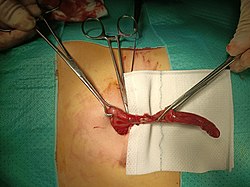

The surgical procedure for the removal of the appendix is called an appendectomy. Appendectomy can be performed through open or laparoscopic surgery. Laparoscopic appendectomy has several advantages over open appendectomy as an intervention for acute appendicitis.[84]

For over a century, laparotomy (open appendectomy) was the standard treatment for acute appendicitis.[85] This procedure consists of the removal of the infected appendix through a single large incision in the lower right area of the abdomen.[86] The incision in a laparotomy is usually 2 to 3 inches (51 to 76 mm) long.

During an open appendectomy, the person with suspected appendicitis is placed under general anesthesia to keep the muscles completely relaxed and to keep the person unconscious. The incision is two to three inches (76 mm) long, and it is made in the right lower abdomen, several inches above the hip bone. Once the incision opens the abdomen cavity, and the appendix is identified, the surgeon removes the infected tissue and cuts the appendix from the surrounding tissue. After careful and close inspection of the infected area, and ensuring there are no signs that surrounding tissues are damaged or infected. In case of complicated appendicitis managed by an emergency open appendectomy, abdominal drainage (a temporary tube from the abdomen to the outside to avoid abscess formation) may be inserted, but this may increase the hospital stay.[87][needs update] The surgeon will start closing the incision. This means sewing the muscles and using surgical staples or stitches to close the skin up. To prevent infections, the incision is covered with a sterile bandage or surgical adhesive.

Laparoscopic appendectomy was introduced in 1983 and has become an increasingly prevalent intervention for acute appendicitis.[88] This surgical procedure consists of making three to four incisions in the abdomen, each 0.25 to 0.5 inches (6.4 to 12.7 mm) long. This type of appendectomy is made by inserting a special surgical tool called a laparoscope into one of the incisions. The laparoscope is connected to a monitor outside the person's body, and it is designed to help the surgeon to inspect the infected area in the abdomen. The other two incisions are made for the specific removal of the appendix by using surgical instruments. Laparoscopic surgery requires general anesthesia, and it can last up to two hours. Laparoscopic appendectomy has several advantages over open appendectomy, including a shorter post-operative recovery, less post-operative pain, and lower superficial surgical site infection rate. However, the occurrence of an intra-abdominal abscess is almost three times more prevalent in laparoscopic appendectomy than open appendectomy.[89]